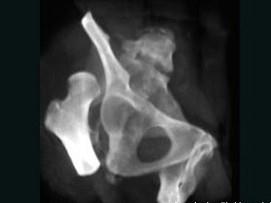

问题 女,19岁,跛行19年,请结合影像学检查,选出最可能的诊断 ( )

选项 A、髋臼骨折 B、股骨头缺血坏死 C、先天性髋内翻 D、骨盆骨折 E、先天性髋关节脱位

答案 E